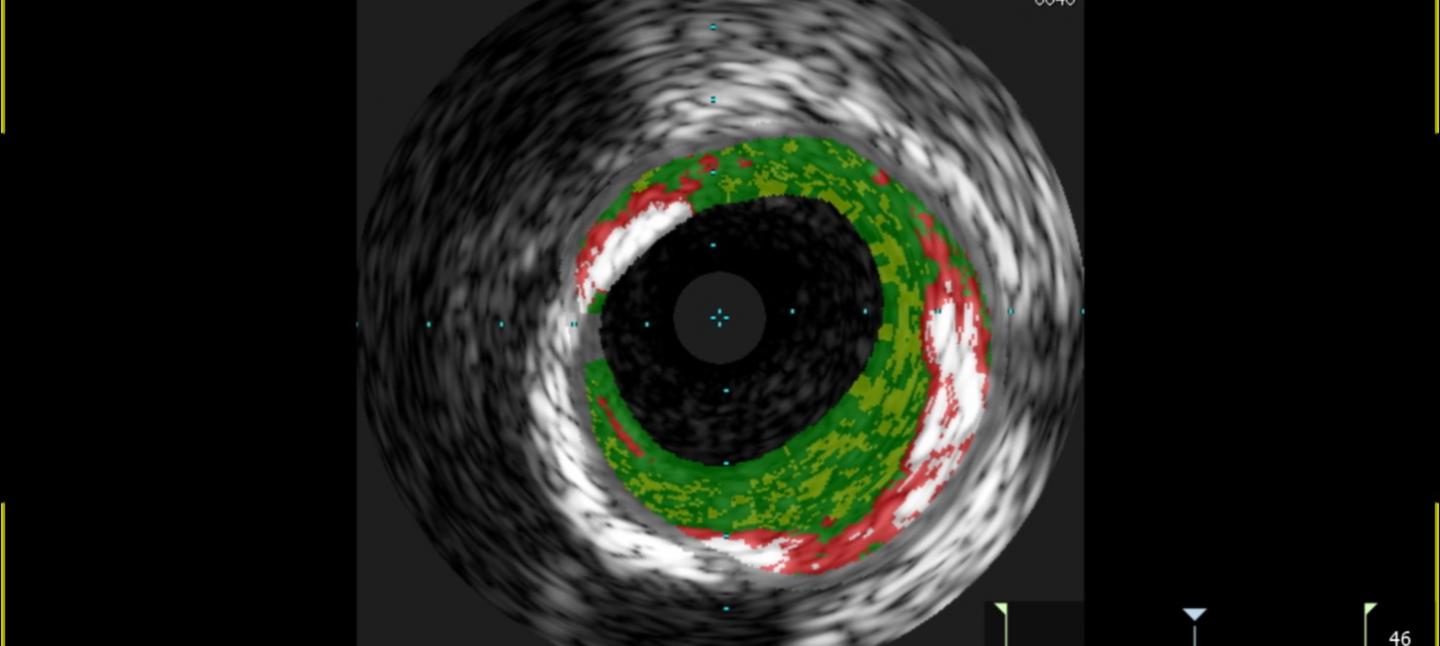

Looking at 118 patients, the researchers determined that those sensitive to the meat allergen had 30 percent more plaque accumulation inside their arteries than those without the sensitivity. Further, the plaques had a higher percentage with features characteristic of unstable plaques that are more likely to cause heart attacks.